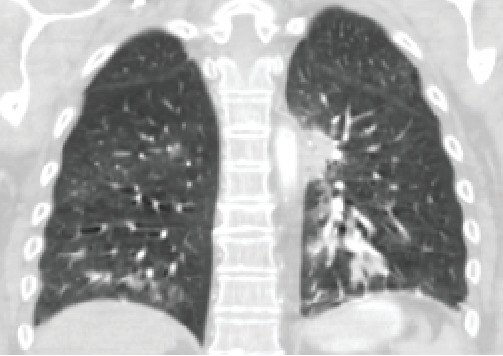

Strongyloides stercoralis is a soil-transmitted roundworm nematode estimated to affect over 600 million people worldwide. Hyperinfection syndrome (HS) has been described in immunosuppressed patients. Our case highlights a rare manifestation of HS due to Strongyloides stercoralis causing acute respiratory failure in an asthma-COPD overlap syndrome (ACOS) patient on chronic corticosteroid therapy. A 63-year-old woman with diabetes, chronic obstructive pulmonary disorder due to chronic cigarette smoking, and severe asthma on chronic prednisone therapy presented with recurrent intractable abdominal pain and shortness of breath. The patient underwent esophagogastroduodenoscopy (EGD) showing friable mucosa returning positive for Strongyloides stercoralis infection. The patient deteriorated with progressive acute hypoxic respiratory failure and acute metabolic encephalopathy requiring invasive mechanical ventilation. Dual antiparasitic therapy with ivermectin and albendazole was initiated, and the patient was treated for septic shock. The patient was successfully extubated and was discharged from the hospital to a rehabilitation center without steroid therapy. Due to the classic transmission and life cycle of the filiform larvae, the lungs are target organs in HS. The mortality of Strongyloides HS ranges from 85% to 100% when untreated. HS due to Strongyloides stercoralis carries a high risk for disseminated infection in patients with chronic steroids. High index of suspicion, tissue sample, and prompt institution of target therapy institutions are key for a successful clinical outcome.